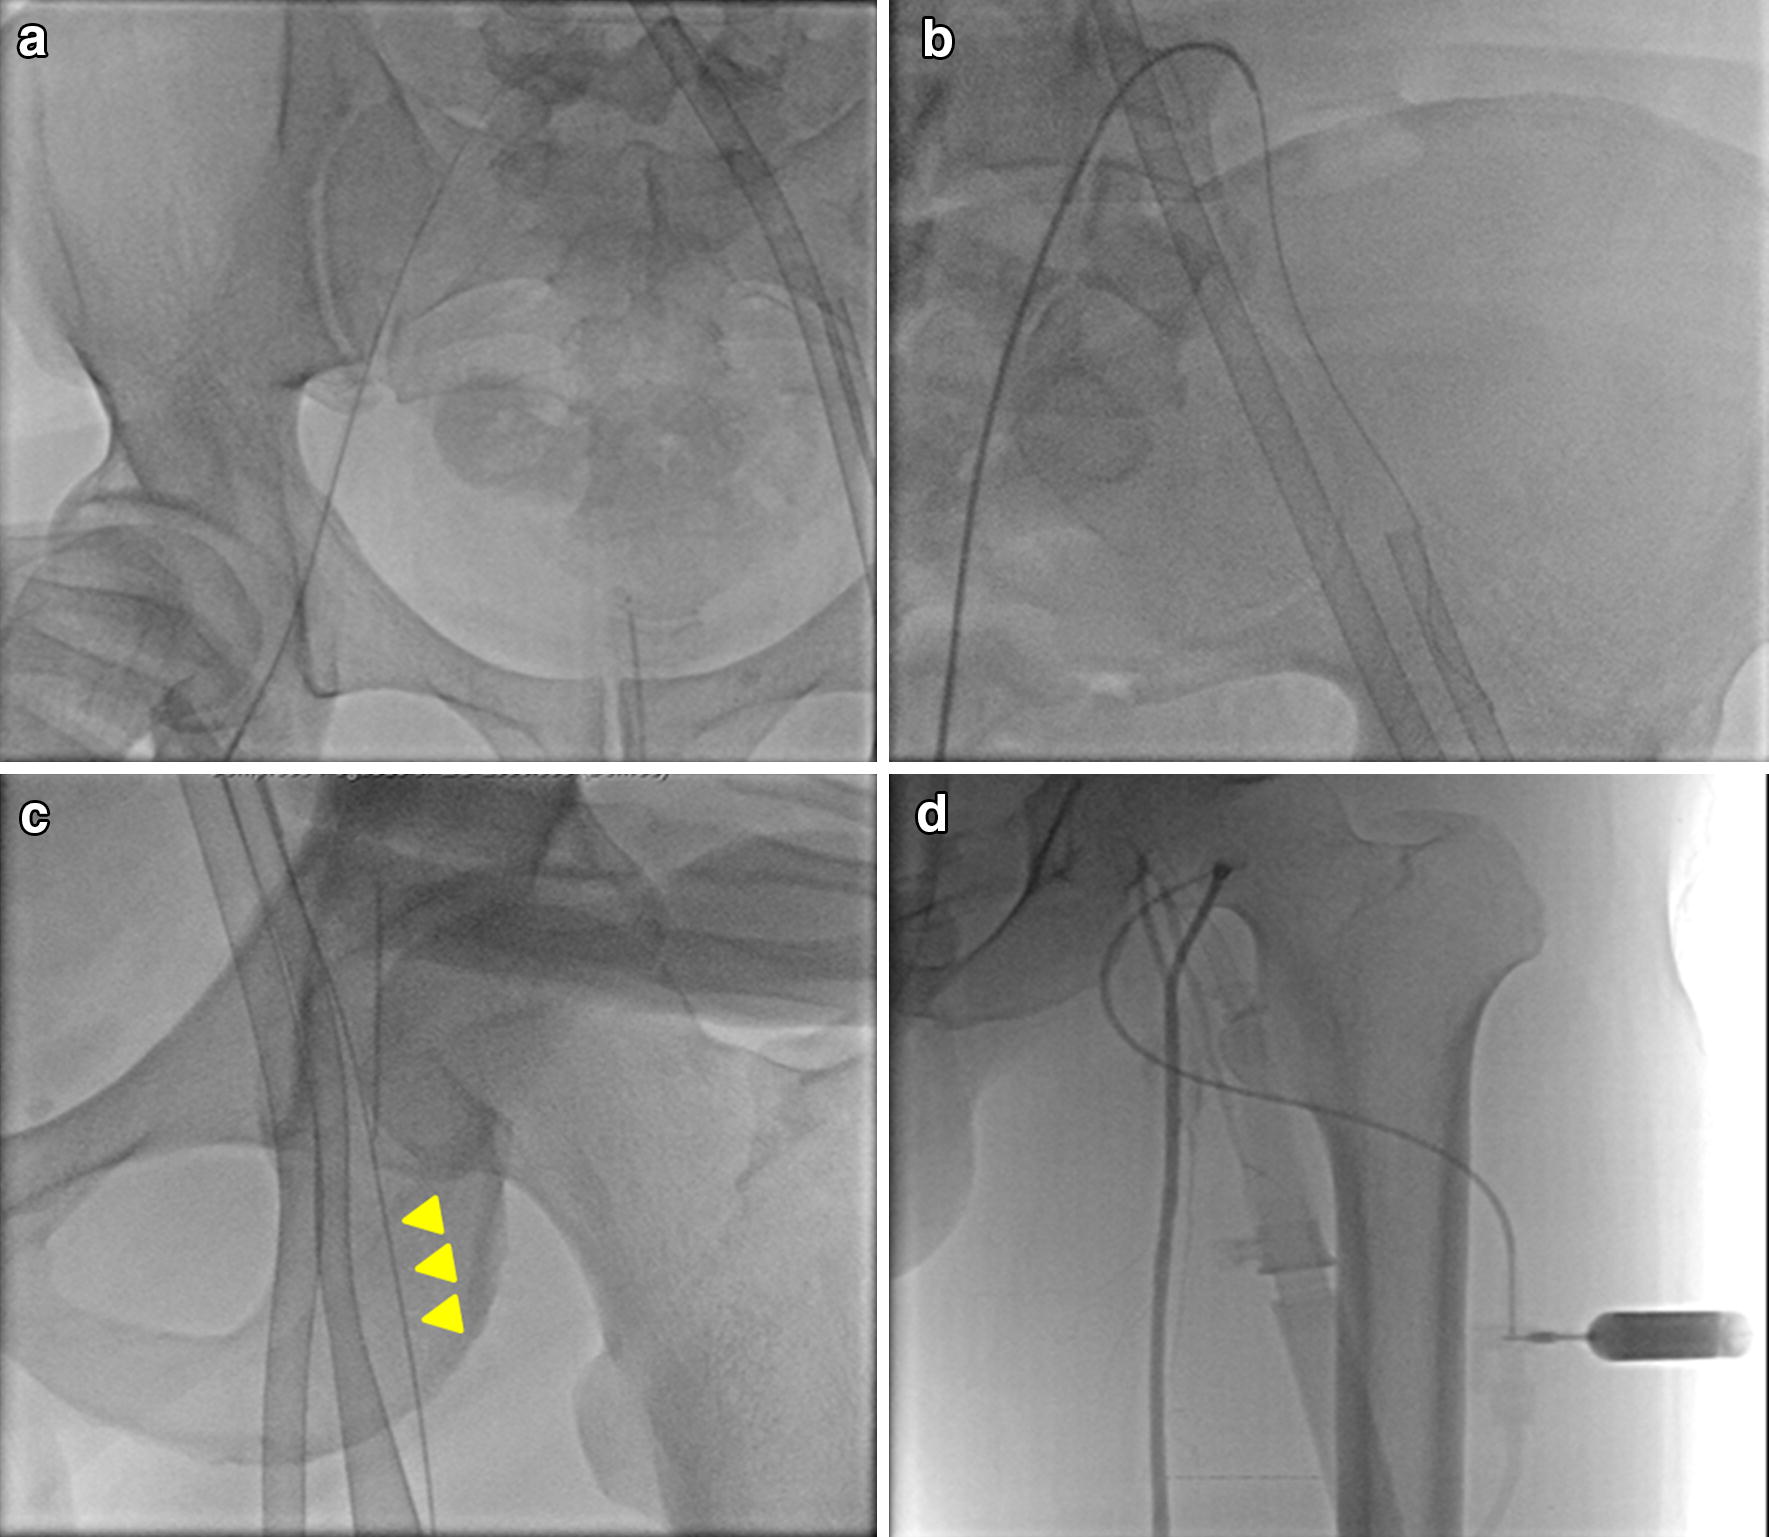

Fig. 2.

Percutaneous insertion of a distal perfusion catheter. a Under fluoroscopy guidance, a sheath at the contralateral common femoral artery (CFA) was inserted using a micropuncture needle followed by a 0.018-inch nitinol wire. b A hydrophilic wire was advanced from the sheath of the contralateral CFA (through the aortic bifurcation and the ipsilateral common iliac artery, between the arterial ECMO cannula and the vessel wall of the ipsilateral common iliac artery) to the distal portion of the ipsilateral superficial femoral artery (SFA). c The proximal SFA ipsilateral to the arterial cannula was punctured using a micropuncture needle followed by a 0.018-inch nitinol wire as the reference point of the previously placed wire (yellow arrow heads). A distal perfusion catheter (6- or 7-Fr. sheath) was inserted antegrade and advanced safely into the mid-SFA. d The distal perfusion catheter was attached to the side port of the arterial cannula using 6-inch extension tubing with an intervening three-way stopcock